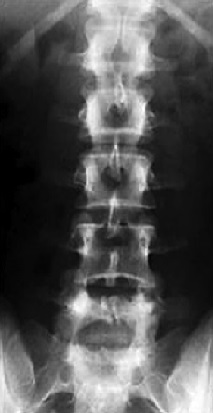

Neck & spine.

Stabbing pain.

Burning sensation.

I can’t move…

Unmovable legs.

Feel nothing.